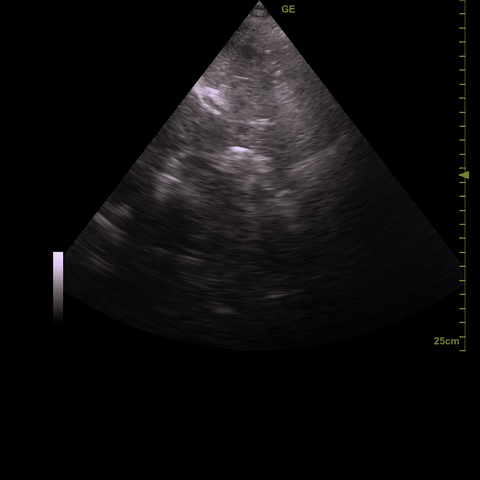

If you see anechoic space “above” the RV free wall (i.e in the near field) and right atria that becomes larger as you scan posteriorly this is a positive scan for effusion. Ideally you would confirm with a second cardiac view but with moderate (1-2 cm) or large (>2 cm) this is not always necessary. This image shows a moderate pericardial effusion.